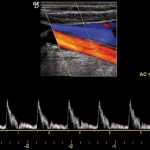

Il test da sforzo, detto anche test ergometrico, prova da sforzo o elettrocardiogramma (ECG) sotto sforzo è un esame che consente di studiare il funzionamento del cuore quando viene sottoposto a uno sforzo fisico; nel test da sforzo cardiopolmonare è valutata anche la risposta dei polmoni.

L’esame viene prescritto dopo aver eseguito altre indagini tra cui: l’elettrocardiogramma, la spirometria o l’ecocardiocolordoppler.

La prova consiste nella registrazione di un elettrocardiogramma, prima a riposo e poi mentre si cammina su un tapis roulant, o si pedala su una cyclette, con livelli di sforzo crescenti.